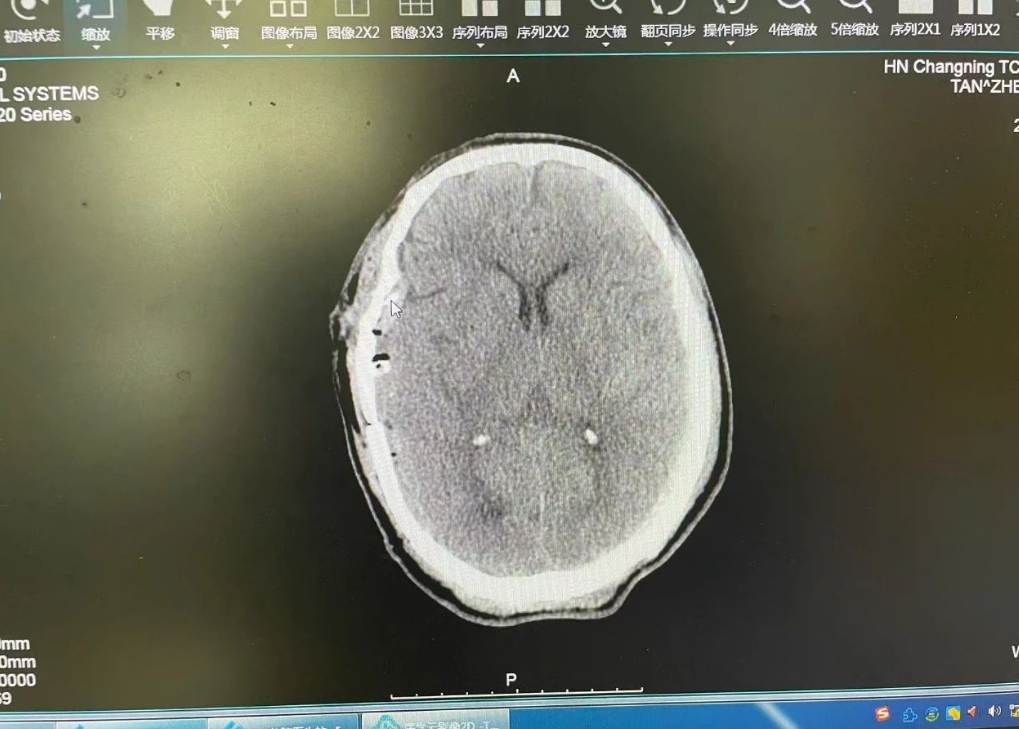

(术前脑部CT片)

“患者右侧颞顶部硬膜外血肿如‘炸弹’,右侧颅骨粉碎性骨折,头部保护屏障受损,双侧肩胛骨粉碎性骨折,肩部活动功能受重创,双侧多发性肋骨骨折,呼吸伴随剧痛,双侧胸腔少量血气胸,左侧肩关节脱位,肢体活动受限,这么重的伤势随时可能引发脑疝危及生命。”脑外科主任段小斌介绍说。